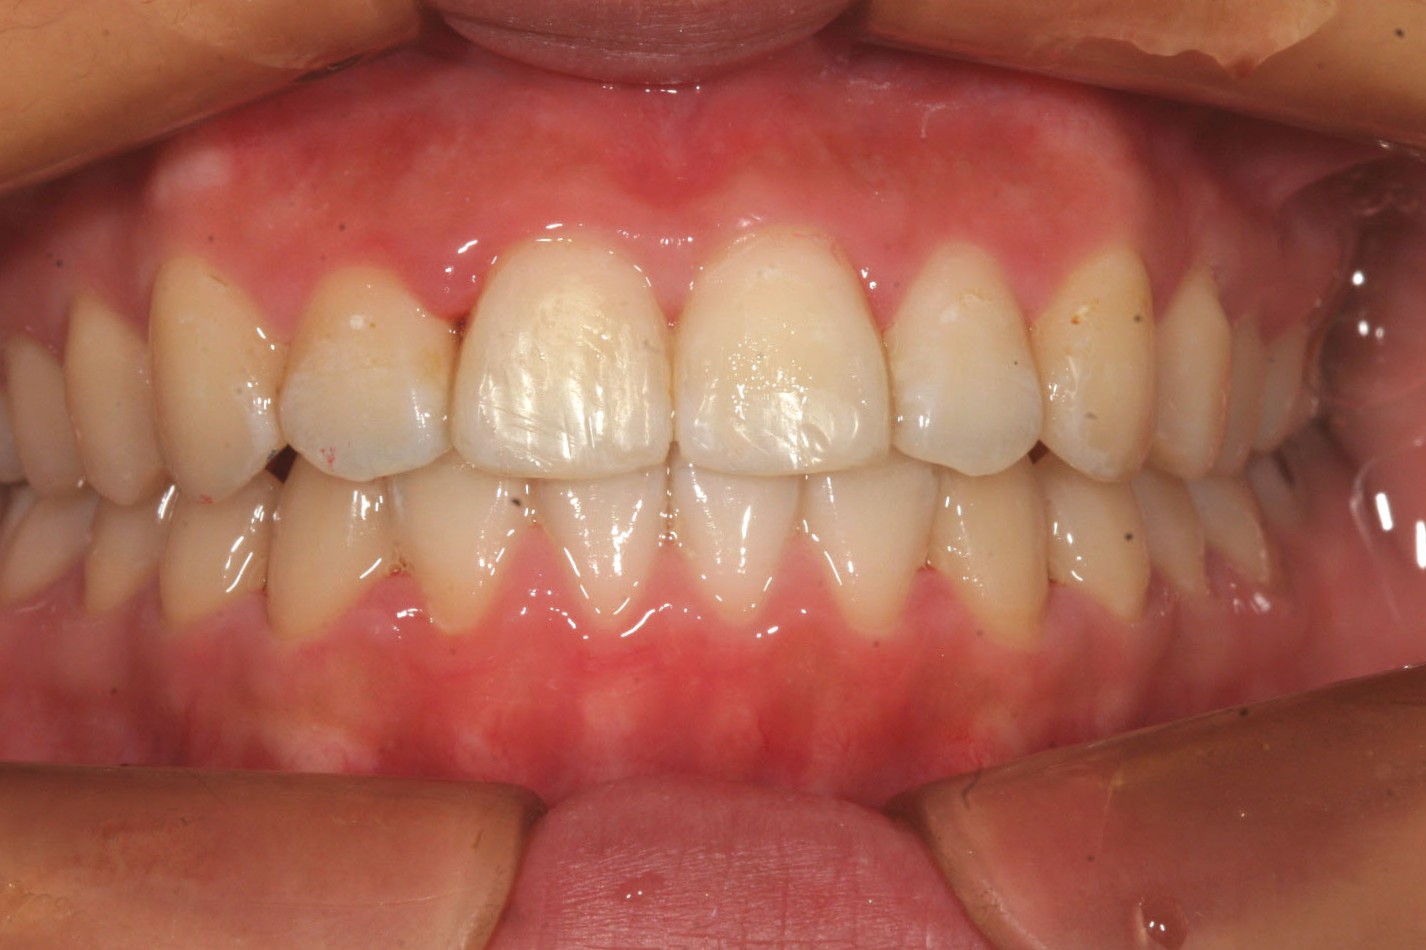

犬歯間を広げた為綺麗に並びました。

下顎も少し犬歯間を広げてます。

オーバージェットも綺麗になりました。

かなりひどい叢生に見えるのですが治療期間を見てお分かり頂けますように、さほど難症例では有りません。

きっちり真面目にアライナーを入れてチューイーを噛んで頂ければこの様に素晴らしい歯並びが手に入ります。